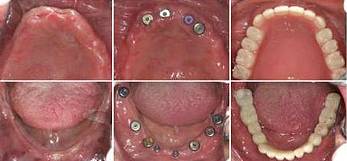

刘先生(花甲之年)牙缺失

步入花甲之年的刘先生其实在40多岁的时候牙齿就开始松动,起初想着还可以凑合吃饭,就没有怎么管,可是如今年纪大了,牙齿一颗接着一颗的掉,只能喝粥。

△种植过程

经过2个多小时的种植过程,刘先生缺牙问题解决了,当天种好恢复咀嚼力。现场露出一口整齐洁白的牙齿,笑着说:“有个孝顺的女儿真是很大的福气,现在终于可以好好的吃一顿饭了。”